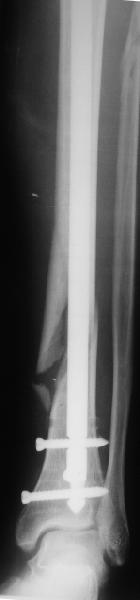

Техника введения штифта в дистальные переломы голени отличается от введения в c/3 диафиз. В дистальном отделе штифт надо ввести поглубже и блокировку внизу сделать на все возможные дистальные отверстия. В верхней части короткий штифт создает запас для будущей динамизации.

Одним из идеальных штифтом для лечения дистальных переломов голени является от Synthes Expert Nail, где имеется 4 возможные отверстия для дистальной блокировки, которые в различных направлениях создают дополнительную стабильность.

На снимке сохранен небольшой вальгус, но имеется нормальная аппозиция медиального кортикального слоя и поэтому трудно согласится что здесь имеется неправильно фиксированный перелом. Для идеального сопоставления таких косых переломов надо открывать фокус травмы, но тогда меняется философия фиксации.

Навряд ли рискованные манипуляции в фокусе травмы или ре-остеосинтез улучшит результат кроме рентгенологической картины.

Для предупреждения осложнении можно оставить как есть, потому что всего месяц с момента операции и не видно признаков несостоятельности остеосинтеза.

Отсутствие болей показания к нагрузке и после восстановления движения в суставе через пару-три недели можно сделать динамизацию. За редким исключением, обычно такие “неправильно фиксированные” переломы сростаются в срок.